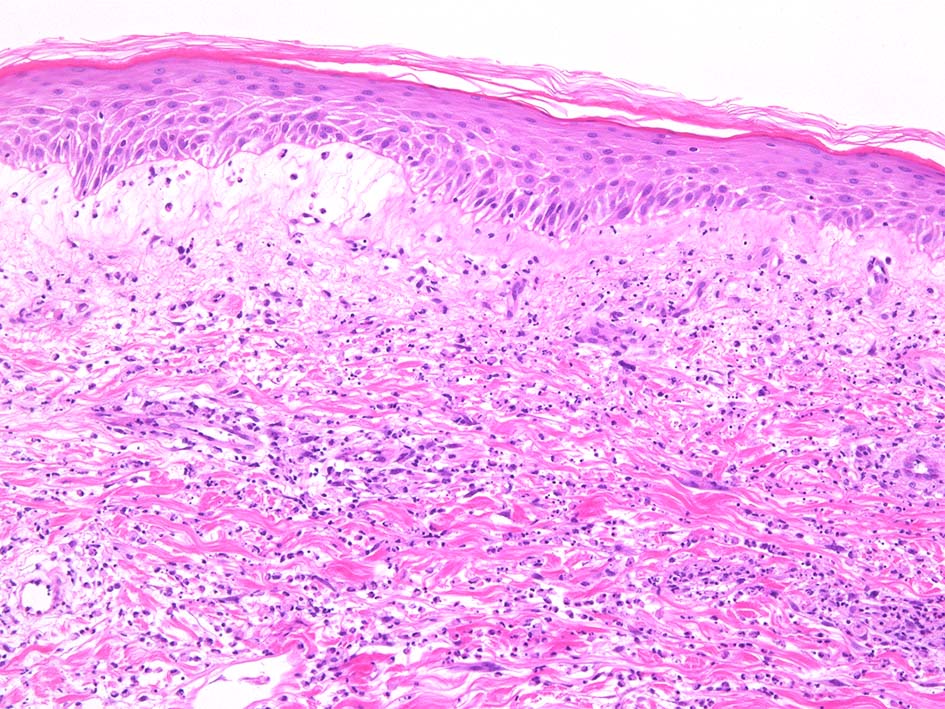

典型疹は真皮の好中球浸潤より始まる. 病初期では, 好中球浸潤は表皮に及ばない. 病期が進むにつれ, 2次的好中球浸潤が認められるようになる.

真皮上中層で広範囲に好中球が密に浸潤する所見がSweet病の最大の特徴. 好中球活性が亢進し, apoptosisを起こして核塵(核破砕物)がみられることが多い. 浸潤が顕著になると真皮上中層が浮腫をきたして, 皮疹が隆起する.

真皮上層浮腫がつよくなり表皮下水疱を形成することがある. 水疱内にはフィブリンや炎症細胞が多数認められる.

真皮の好中球浸潤部には毛細血管, 細動静脈が巻き込まれるが, 血管のフィブリノイド壊死は認められない.(鑑別が難しいことのあるBehçet病では2012年より, 壊死性血管炎があるとされており鑑別のための病理所見となっている)

表皮基底層の液状変性, また液状変性ほど強くなくともvesicleの形成が見られることがある.

HE x40. Sweet病最盛期皮膚病変の所見があります.

表皮下水疱, 真皮上層の細血管周囲に密な好中球浸潤あり.(thumb nail clickで大きなphotoが見られます)